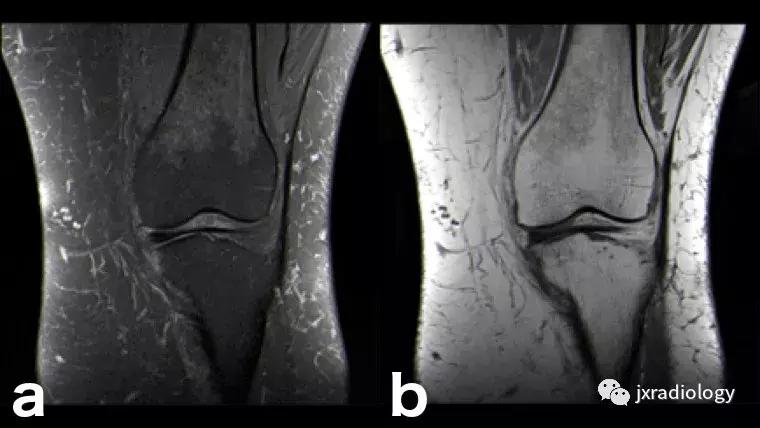

图28:正常的红骨髓:这是寻找骨髓水肿时可能出现的误区。造血系统红骨髓(由于年轻患者正常分布或成人骨髓再生)在T1-WI(b)和水敏序列(a:PD-FS-WI)上均具有中等信号强度。T1-WI上的正常红骨髓相对于肌肉的分布(通常在干骺端)的特征性模式和较高的信号强度(与T1-WI上肌肉组织的等信号或低信号的病理性骨髓相反),应能及时发现这一正常发现。